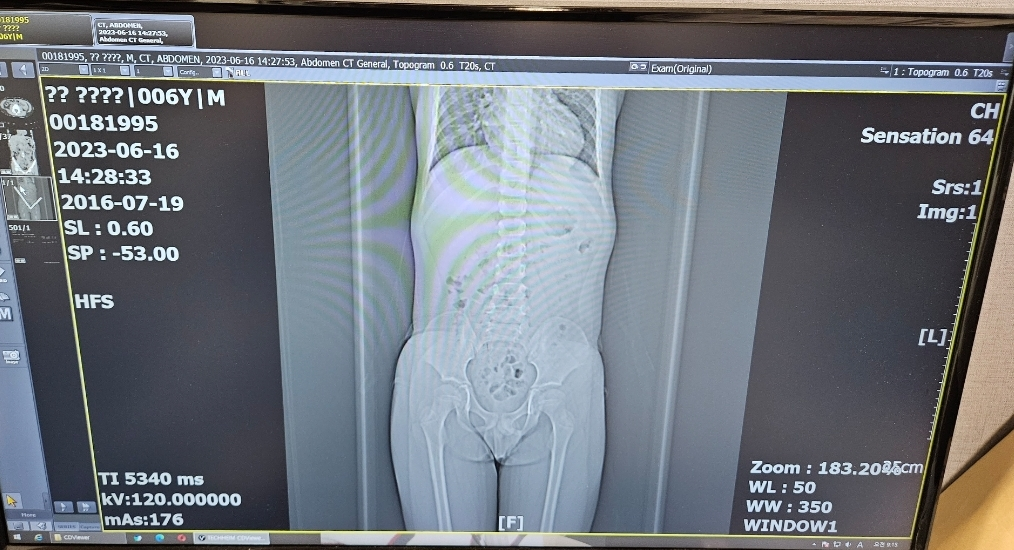

복부 ct 방사선 피폭량 문의드립니다.

6살 아이가 씨티를 오늘 찍었습니다.

어린이 전문병원이 아닌 성인들이 주로가는 병원에서

찍었는데 위 사진과 같이 마지막 슬라이드가 있는데

피폭 방사선량이 몇 mSv인지 알수 있을까요?

복부는 기본적으로 10~15 mSv로 알고있는데

아이한테는 더 적게 쏘인건지 궁금합니다.

그리고 몸이 작아서 그런지 복부 외에 목아래

흉부 척추 생식기쪽도 다 찍어져있더라구요.

전체 다 피폭된건지도 궁금합니다.

올려주신 사진으로 계산해보니 5mSv 정도로 계산이 되네요.

두번째 사진의 흉부와 생식기쪽 및 허벅지까지 찍힌 것은 topogram으로 ct를 본격적으로 찍기전 한번 쓰윽 스캔해서 여기부터 여기까지 찍으라고 설정하기위한 사진이므로 피폭걱정은 하지않으셔도 됩니다.

원래 복부 CT는 Abdomino-pelvic CT라 부르는데, 흉부의 아랫부분에서 시작해서 대퇴부위의 일부까지 찍는 것이 일반적입니다. 범위는 적절하다고 볼 수 있고, 노출된 방사선량은 사진의 DLP를 기준으로 볼 때 5-6mSv 정도 됩니다.

CT중 피폭량이 큰 복부 CT도 2-4mSv정도의 방사선에 노출됩니다. 10-15mSv만큼 노출되지 않습니다.

인체에 유해할 수 있는 방사선량은 1년에 100mSv 이상 노출되었을 때 정도로 생각하시면 되기 때문에 전혀 걱정하실 상황이 아닙니다.

단면 씨티가 어디까지 찍어져있는지가 중요하겠고 이때 주로 방사선에 노출됩니다. 올려주신 사진중에 아래사진을 찍을때는 이야기 하시듯 흉부와 생식기까지 다 촬영을 하기는 했네요.